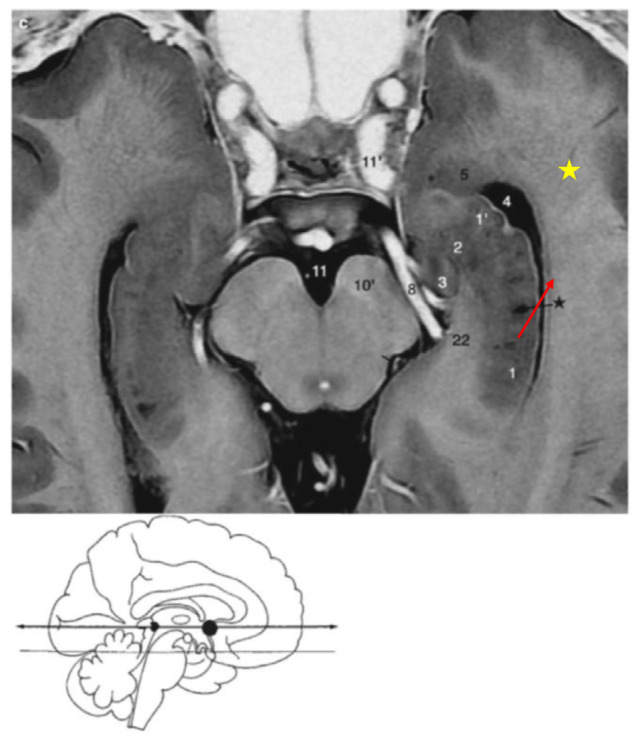

Delineating Neuroanatomical Structures for the Measurement of Temporal Horn Dilatation.